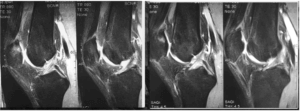

В качестве примера, иллюстрирующего регенеративные свойства педлагаемой методики леения приостеоартрозах, ниже приводим МРТ-динамику пациента с гонартрозом, сопровождающимся хон- дромаляцией и костным отеком надколенника (рис. 3,4).

Рис.3 Хондромаляция надколенника с костным отеком до MBST- терапии 09.2016г

Рис. 4 Регенерация хрящевых и костных структур через 6 месяцев после MBST-терапии 03.2017г.